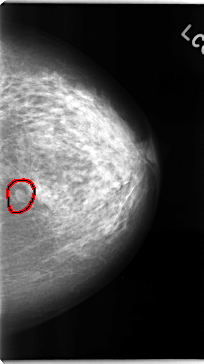

FILE: C_0102_1.LEFT_CC.OVERLAY

TOTAL_ABNORMALITIES 1

ABNORMALITY 1

LESION_TYPE MASS SHAPE OVAL MARGINS CIRCUMSCRIBED

ASSESSMENT 3

SUBTLETY 5

PATHOLOGY BENIGN

TOTAL_OUTLINES 1

BOUNDARY